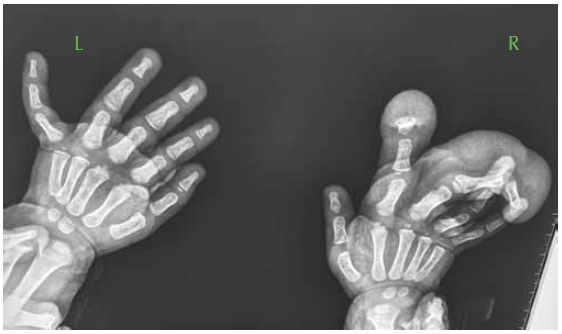

Fig. 2. Macrodactyly of fingers 2–4 of the right hand in a child of two years: a, b — appearance before the surgery; c — radiograph of the hand

Fig. 3. Stages of surgical intervention

Fig. 4. The appearance of the hand and radiograph at the end of surgery

Fig. 5. Appearance of the hand of a child of 1.5 years of age having macrodactyly of the right hand

Fig. 6. Radiograph of the hand of a child of 1.5 years of age with macrodactyly of the right hand

Fig. 7. Stages of surgery

Fig. 8. Appearance and radiograph by the end of the surgery